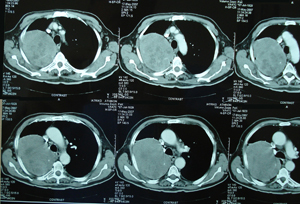

Εικόνα 1

Οπισθιο-προσθία ακτινογραφία θώρακος. Διακρίνεται ευμεγέθης ομοιογενής σκίαση στο δεξιό ημιθωράκιο στο άνω και μέσο πνευμονικό πεδίο.